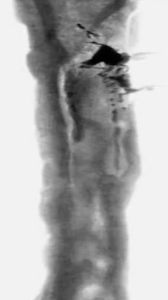

На рентгенограммах левого бедра в 2-х проекциях: консолидированный перелом дистального отдела левой бедренной кости, неоднородность, дефект костной ткани по латеральной поверхности диафиза с выраженной периостальной реакцией на данном уровне. Остеопороз (рис. 1, б).

Мультиспиральная компьютерная томография (МСКТ). Полость в средней трети костномозгового канала бедренной кости с неровным внутренним контуром, протяженностью до 9 см, и на этом протяжении дефект кортикальной пластинки по передненаружной поверхности. Плотность кортикала на уровне полости около 1100 ед. Н. В задних отделах кортикала дефект, замещенный пористым субстратом, размером 2 х 2 х 35 см (губчатая кость имплантат). В центральных отделах дистального метадиафиза линейный аваскулярный секвестр размером 0,65 х 7,5 см (рис. 1, в).